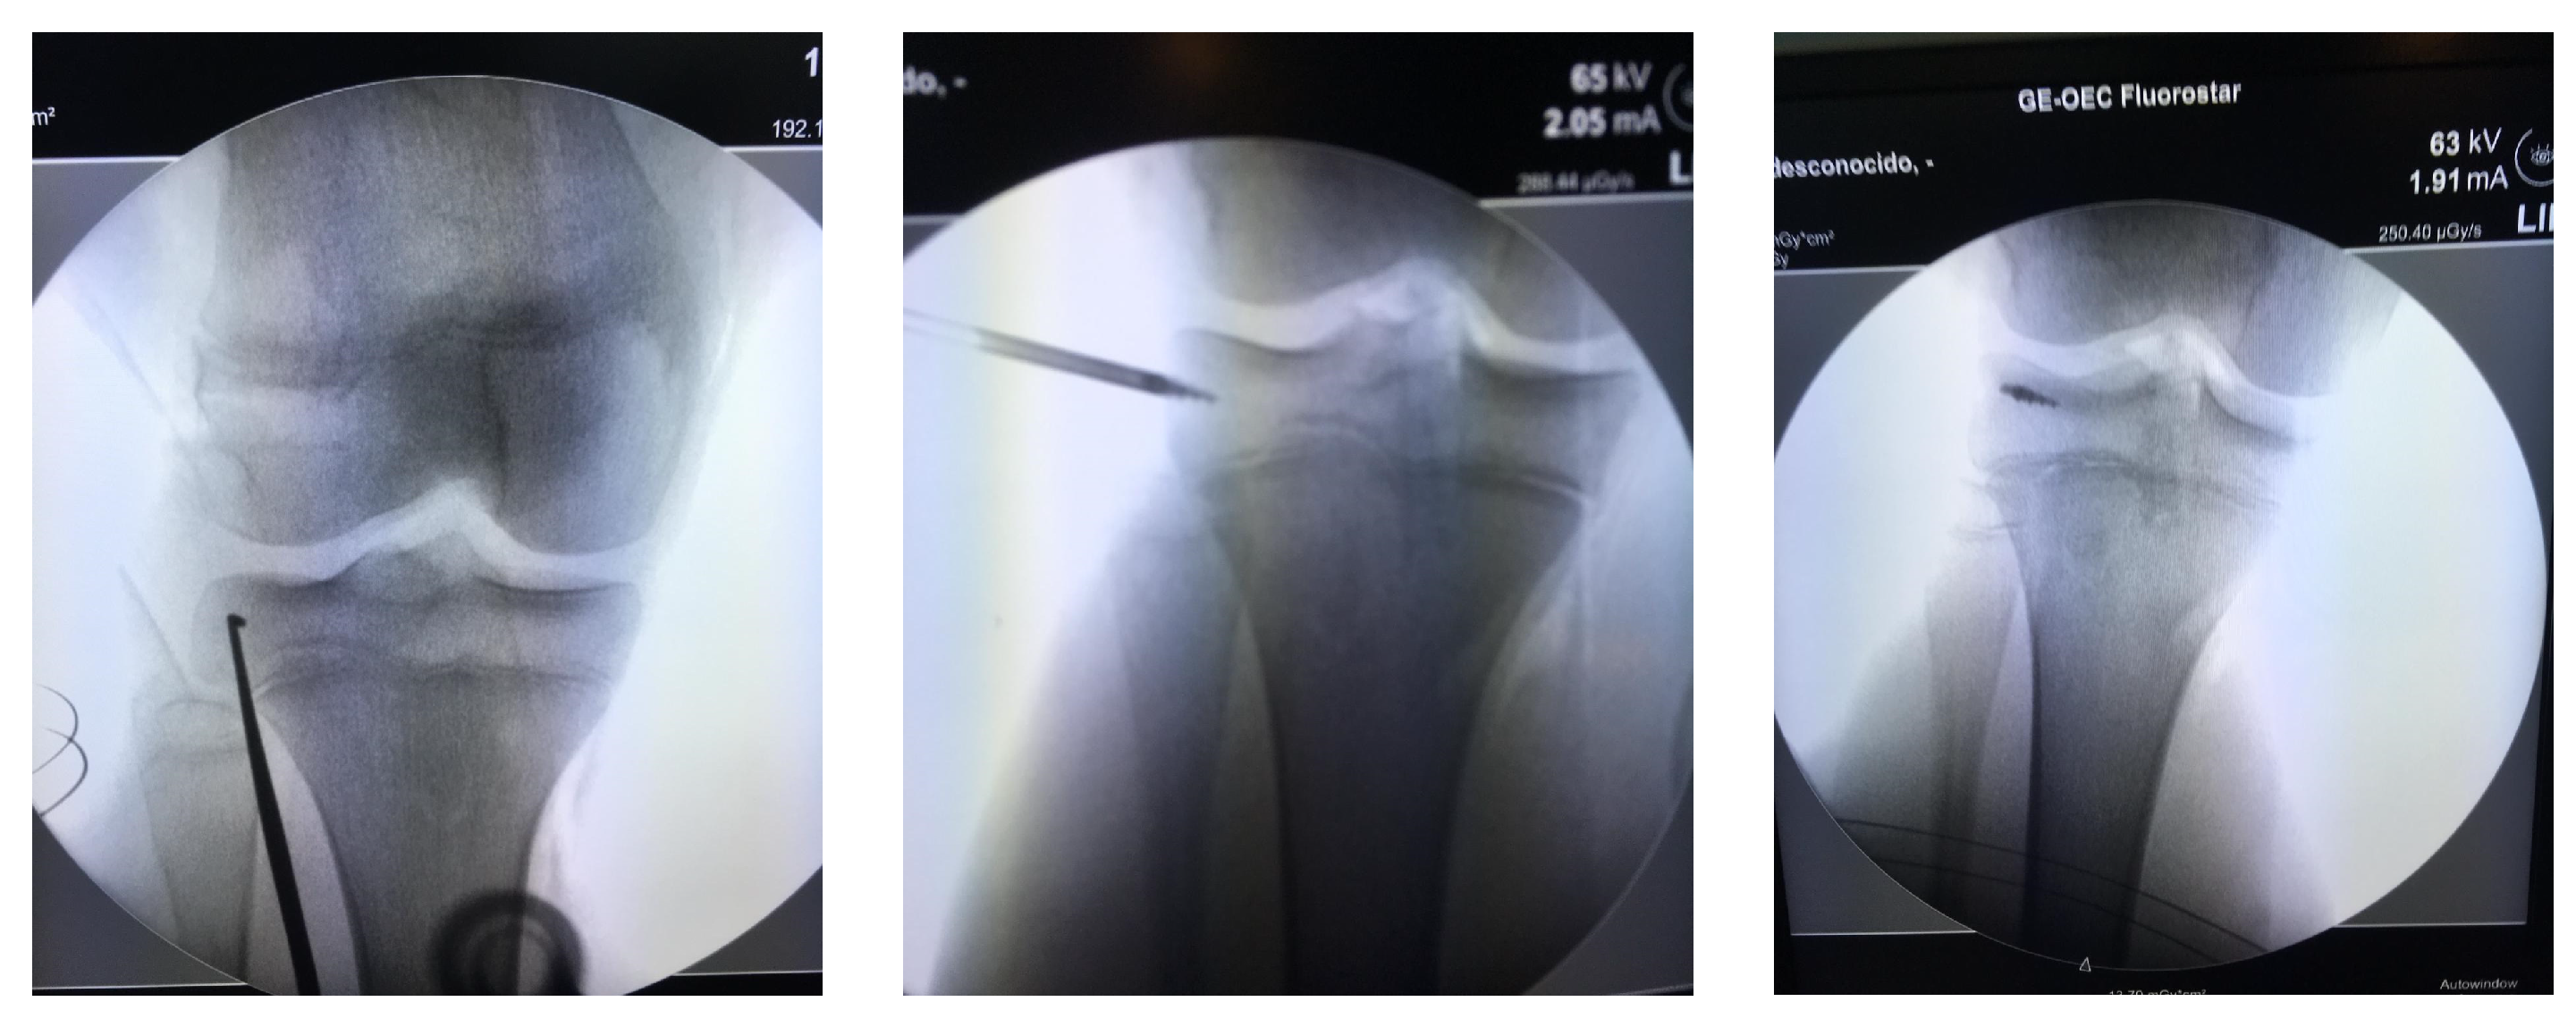

Indications for surgery included 24 patients with LET during Anterior Cruciate Ligament (ACL) reconstruction (in anterolateral margin of the proximal tibia at half of distance between head of fibula and Gerdy´s tubercle), two patients with extra-capsular MPFL reconstruction (on the medial margin of the patella´s border), three patients with quadriceps or patellar tendon repair (inside of the respective bone), and four with MCL repair (on the medial aspect of the proximal tibia, or close to the epicondyle targeting the anatomic footprint of MCL) (Figure 2).

Figure 2. TWINFIX on the epicondyle footprint for medial collateral ligament, at the time of Anterior Cruciate Ligament ACL reconstruction.